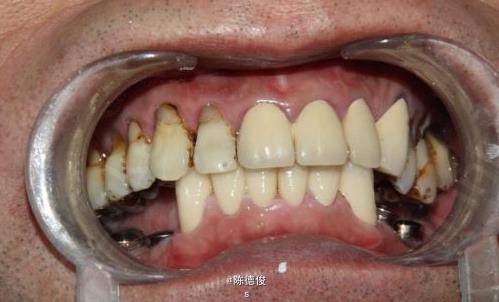

男,64岁,下颌多颗牙缺失数年,身体健康,无烟酒嗜好。

诊断:肯氏1类缺失 诊疗方案:种植固定桥修复+咬合重建 种植系统:瑞士ITI-Straumann种植系统 治疗周期:3个月